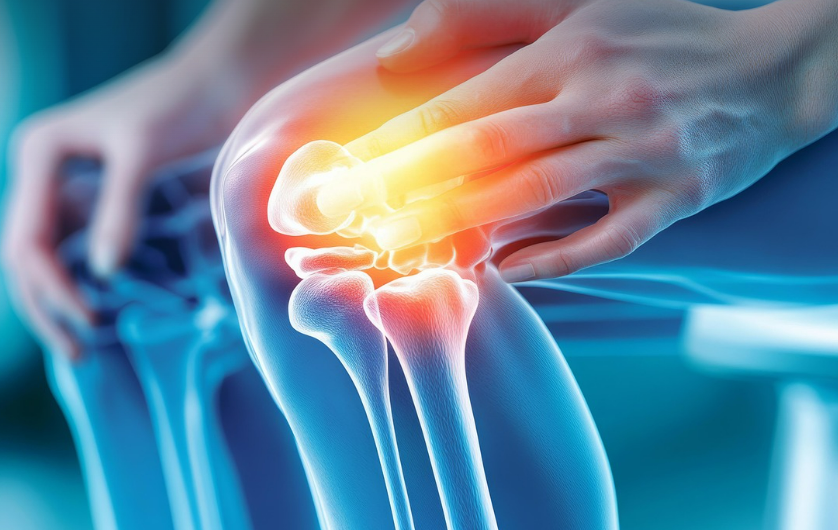

나이가 들수록 가장 먼저 느껴지는 변화 중 하나가 바로 ‘무릎 통증’입니다. 계단을 오르내릴 때, 쪼그려 앉을 때 무릎이 시큰거리고 삐걱대는 느낌이 든다면 연골의 손상이 시작된 것일 수 있습니다. 이런 증상을 완화하기 위해 많은 분들이 찾는 성분이 바로 콘드로이친(Chondroitin) 입니다. 그렇다면 이 성분이 정말 관절 통증에 효과가 있을까요? 과학적 근거를 바탕으로 콘드로이친의 효능과 한계를 정리해봤습니다.

콘드로이친은 연골을 구성하는 대표적인 다당류 성분으로, 관절을 보호하고 윤활 기능을 유지하는 데 중요한 역할을 합니다. 쉽게 말해 연골 속 ‘쿠션’ 역할을 하는 물질로, 충격을 흡수하고 관절이 부드럽게 움직이도록 돕습니다.

콘드로이친은 연골 내 수분을 유지해 마찰을 줄이고, 손상된 연골 조직의 재생을 돕습니다. 이는 노화나 과도한 운동으로 약해진 관절에 특히 도움이 됩니다.

연골이 닳으면 염증 반응이 생기고 통증이 발생하는데, 콘드로이친은 염증 매개 물질의 생성을 억제해 통증을 줄이는 데 기여합니다. 특히 퇴행성 관절염 환자에게 통증 감소 효과가 관찰된 바 있습니다.

콘드로이친은 관절액의 점도를 높여 관절 움직임을 부드럽게 해줍니다. 쉽게 말해 ‘관절의 미끄러짐’을 원활하게 만들어 일상생활 중 불편감을 줄여주는 역할을 합니다.